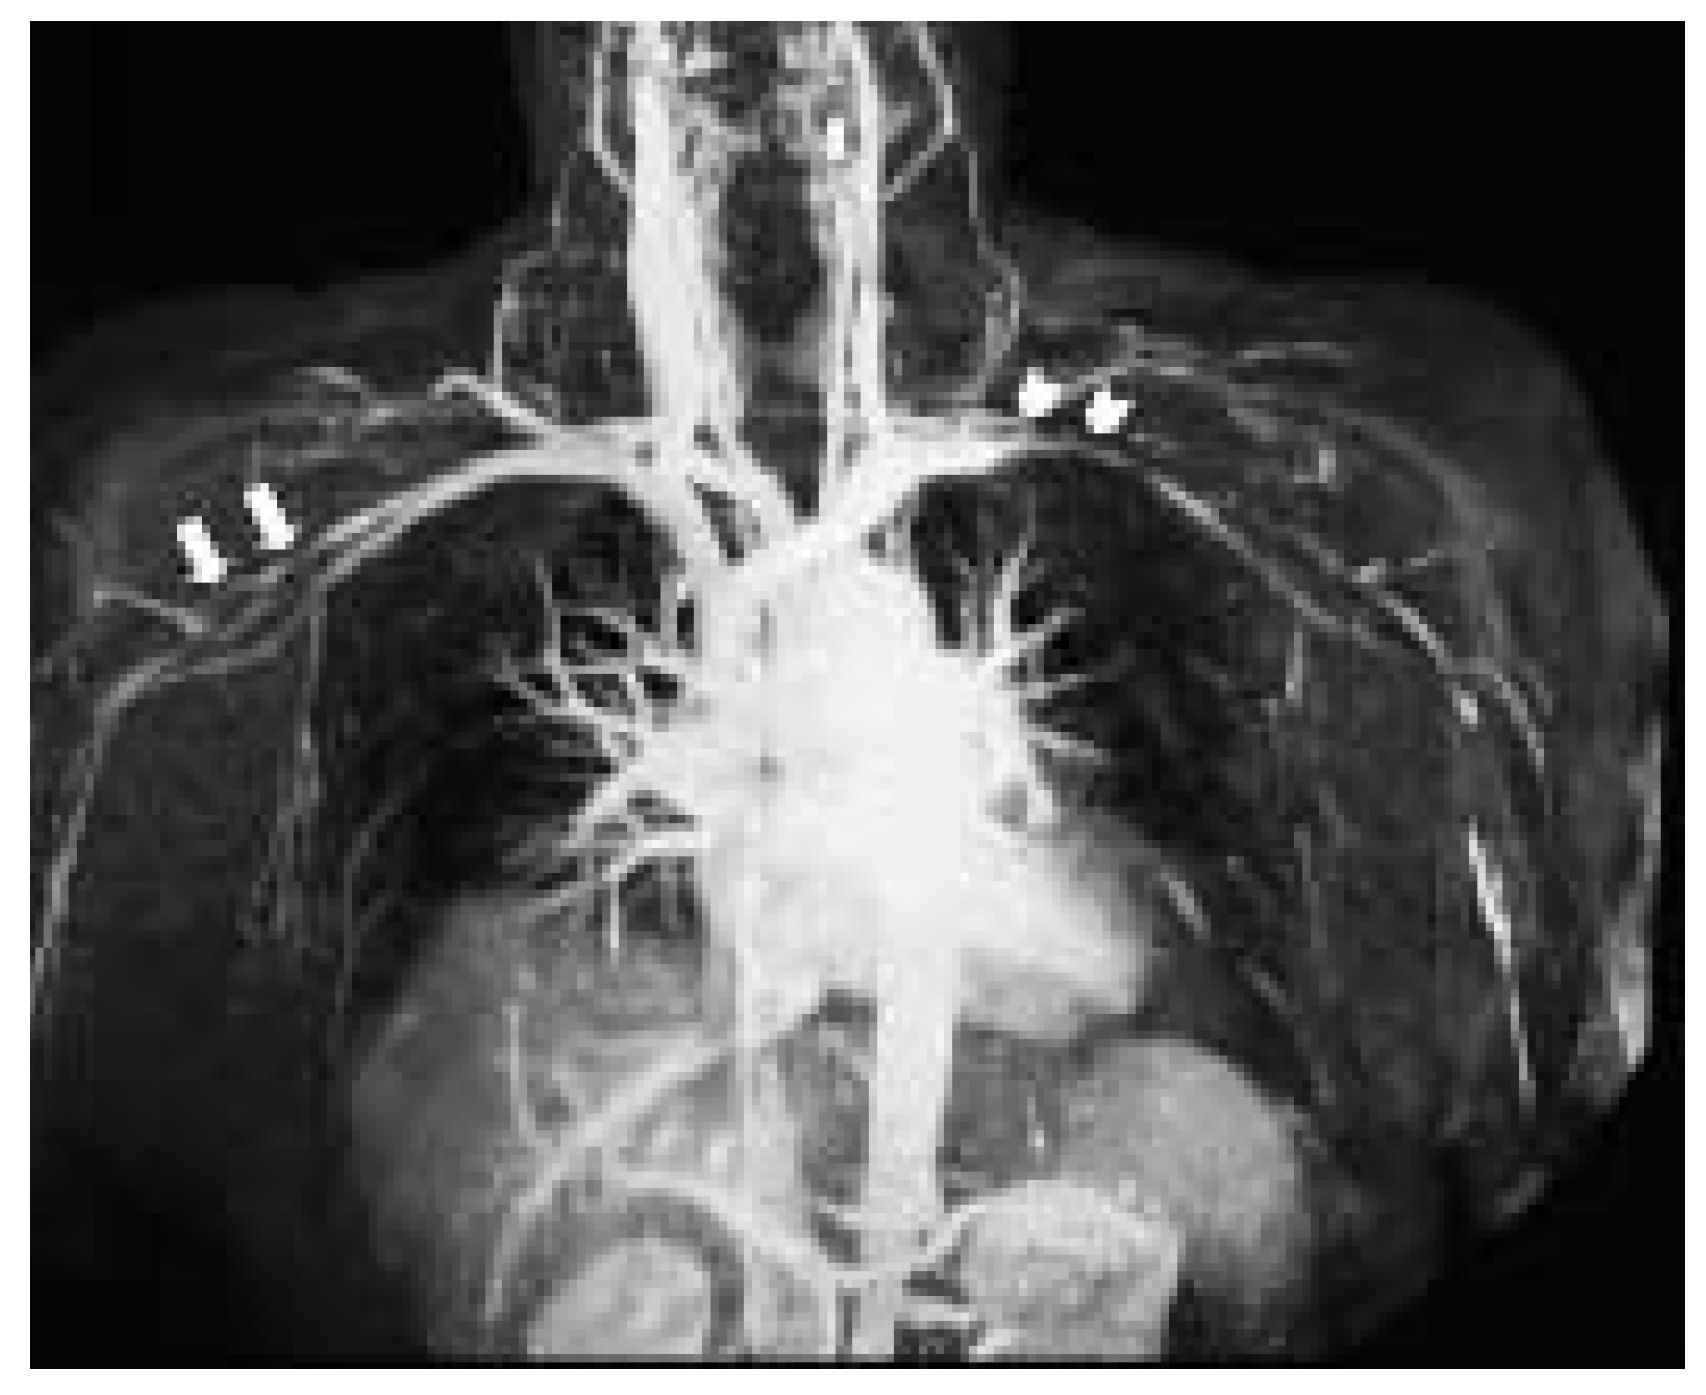

Subclavian and Axillary Giant Cell Arteritis After Influenza Vaccine

Case report